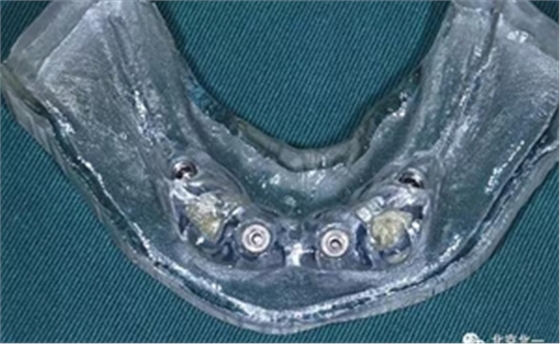

圖三:終末導(dǎo)板

圖四:導(dǎo)板工具